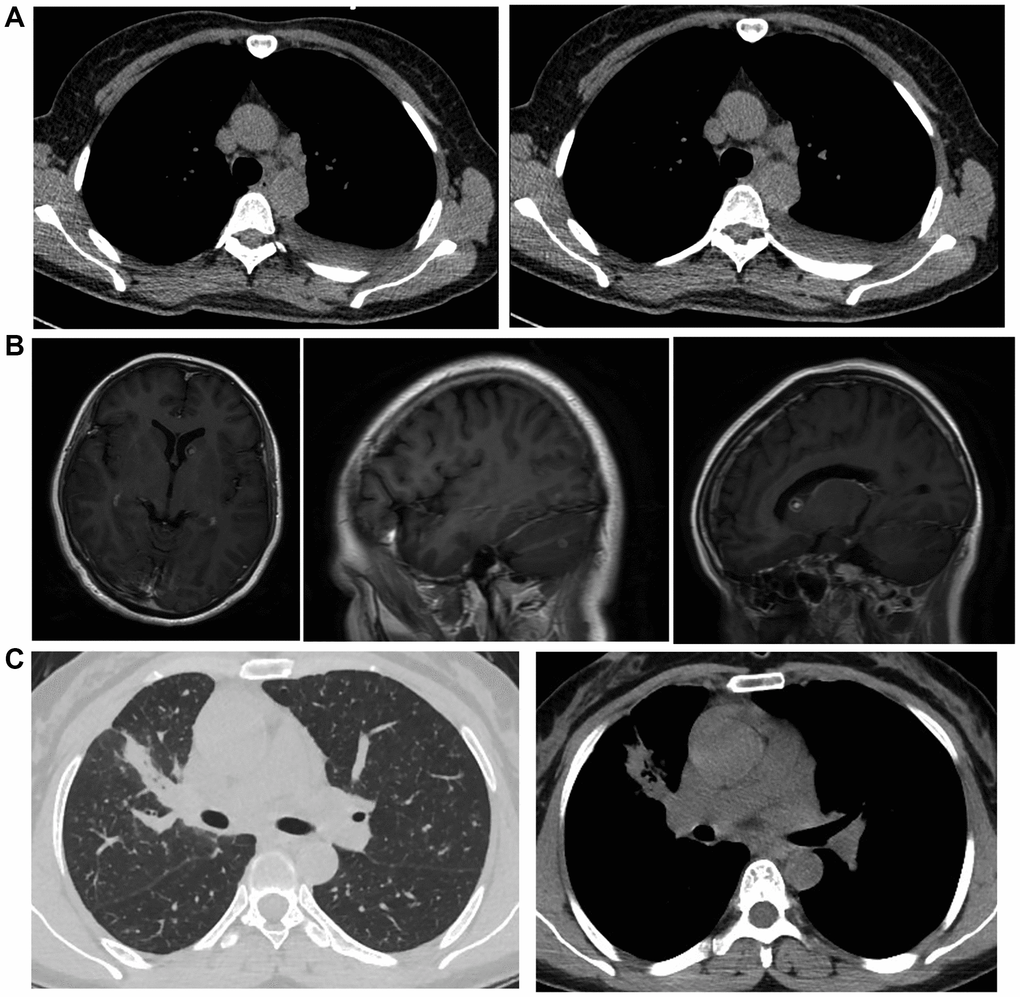

This study recruited 135 patients with brain metastatic lung cancer who were diagnosed with magnetic resonance imaging (MRI) technology (Figure 1) and collected the tissue samples from all of the patients. Genotyping was carried out to determine the genotypes of rs11227209, rs619586, rs664589 and rs3200401 located in MALAT1. The patients were grouped according to their genotypes of MALAT1: 1. CACC (N = 65), 2. GGGT (N = 28), 3. CGCC (N = 16), 4. CAGC (N = 7), 5. GAGT (N = 3), 6. CA (N = 12). The basic characteristics including age at diagnosis, gender, cigarette use history, primary disease history and overall stage of tumor of the patients in the six groups were collected. Then, among all variables, continuous variables were expressed in median, while discrete variables were expressed in the number of cases and percentage. In order to find variables that are linked to the incidence of asymptomatic brain metastasis, SPSS 22.0 (Version number 22.0, IBM, SPSS Inc., Chicago, IL, USA) was utilized. In addition, univariate as well as multivariate logistic regressions were carried out to evaluate the effects of subsequent factors: History of cigarette smoking, largest size of the mediastinal lymph node, and the optimal dissection point for the largest lymph node. Finally, peripheral blood and lung cancer tissue samples were collected from the patients to analyze the expression of target genes. Institutional ethical committee has approved the protocol of this study. Written informed consent was obtained from each patient before the initiation of this study.

Figure 1. The MRI images of metastatic lung cancer patients. (A) MRI image of mediastinal lymph node metastasis and left side pleural effusion. (B) MRI image of brain metastatic non-small cell lung cancer. (C) MRI image of non-small cell lung cancer in the upper lobe of the right lung with metastasis in both lungs and mediastinum.